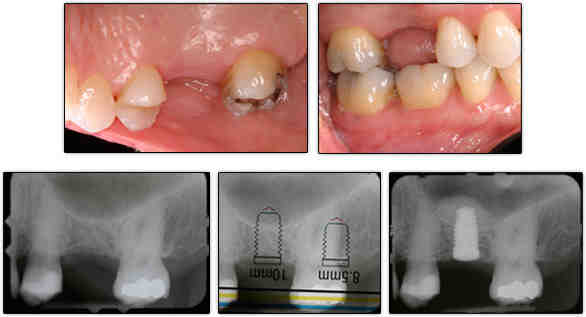

Can I get an implant without a bone graft?

Implants placed in the extraction sockets of infectious teeth also had acceptable survival rates and clinical success. Conclusion: With proper patient selection, immediate implant placement without bone transplantation has predictable survival rates and clinical success.